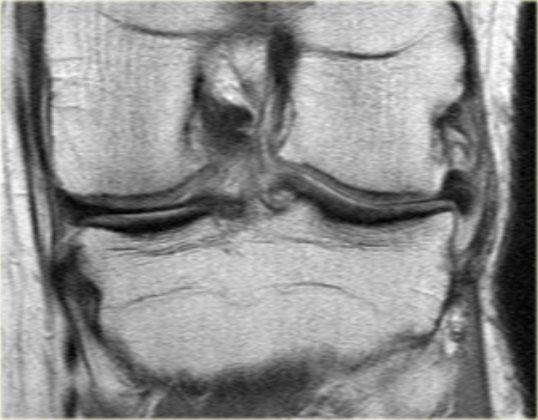

Ghi nhận một đường rách hướng tâm tại vị trí chân sụn chêm phía sau của sụn chêm trong, đường rách xuyên suốt toàn bộ chiều dày sụn chêm với hình ảnh khe dịch lan dọc theo khuyết tổn thương (mũi tên đỏ).

Rách chân sụn chêm thường đi kèm với hiện tượng thoát vị sụn chêm ra ngoài bờ mâm chày.

Thoát vị sụn chêm trên 3 mm thường liên quan đến các tổn thương rách tại vùng chân sụn chêm (6).

Trong trường hợp bên trái, ghi nhận một đường rách hướng tâm hoàn toàn tách rời sừng sau khỏi chân bám của nó (mũi tên đỏ).

Ngoài ra còn có hình ảnh thoát vị sụn chêm mức độ tối thiểu (hình 1/6).

Đây là một trường hợp rách chân sụn chêm trong khác.

Lưu ý rằng sừng sau không còn bám vào xương chày.

Thay vào đó, có thể thấy một khoảng hở (mũi tên cong).

Những tổn thương rách này rất dễ bị bỏ sót khi người đọc nhầm tưởng sừng sau vẫn bình thường.